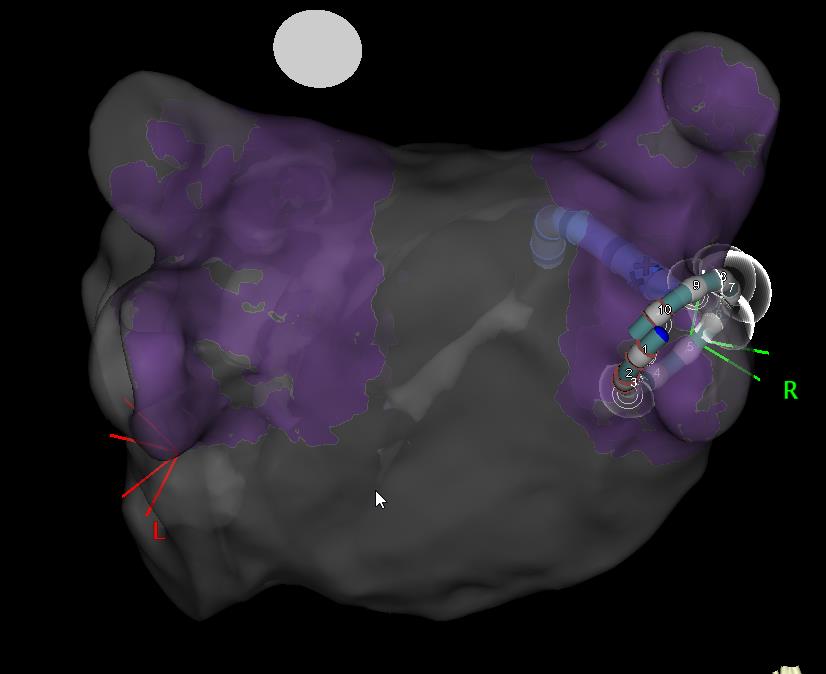

There are now three main technologies available to perform catheter ablation for atrial fibrillation (AF). Cryoablation (panel 2) employs a freezing balloon, whereas radiofrequency (RF) ablation involves delivering a series of small burns to deliver treatment. This is done using an electro-anatomic mapping system to re-create the geometry (i.e. a 3D shell) of the chamber in question – in this case the left atrium- and this can be used to delineate where ablation has been performed (see panel 3).